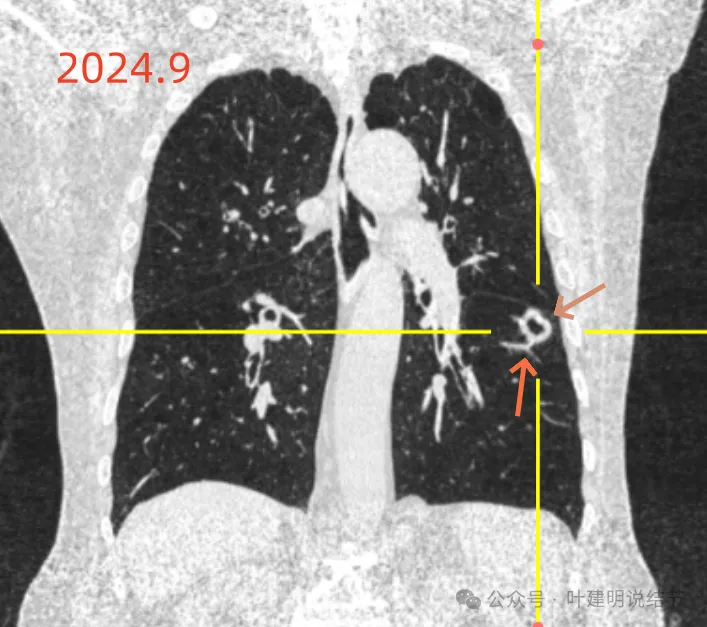

冠状位见病灶基本实性,小血管进入明显,囊壁厚薄不均,囊腔内壁不光滑,表面浅分叶。